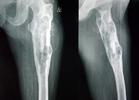

X線所見原發軟骨病變通常表現為骨的中度膨脹,皮質骨增厚,骨性分界明顯,腫瘤內有典型的鈣化。進展的病變表現為進行性的溶骨病變,少數為進行性的成骨病變,原有鈣化消失,皮質骨破壞,侵犯軟組織。有時,僅見一新的進展性腫瘤,其放射影像類似於成人期的各種惡性度高的溶骨性腫瘤。只有得到以前的X線片和對整個腫瘤進行組織學檢查,才能發現原有的惡性度低的軟骨腫瘤的痕跡。相反,在其他病例,影像學和大體病理與普通中心性軟骨肉瘤相同,僅可在組織切片上的幾個有限的區域顯示出新的惡性高的肉瘤。